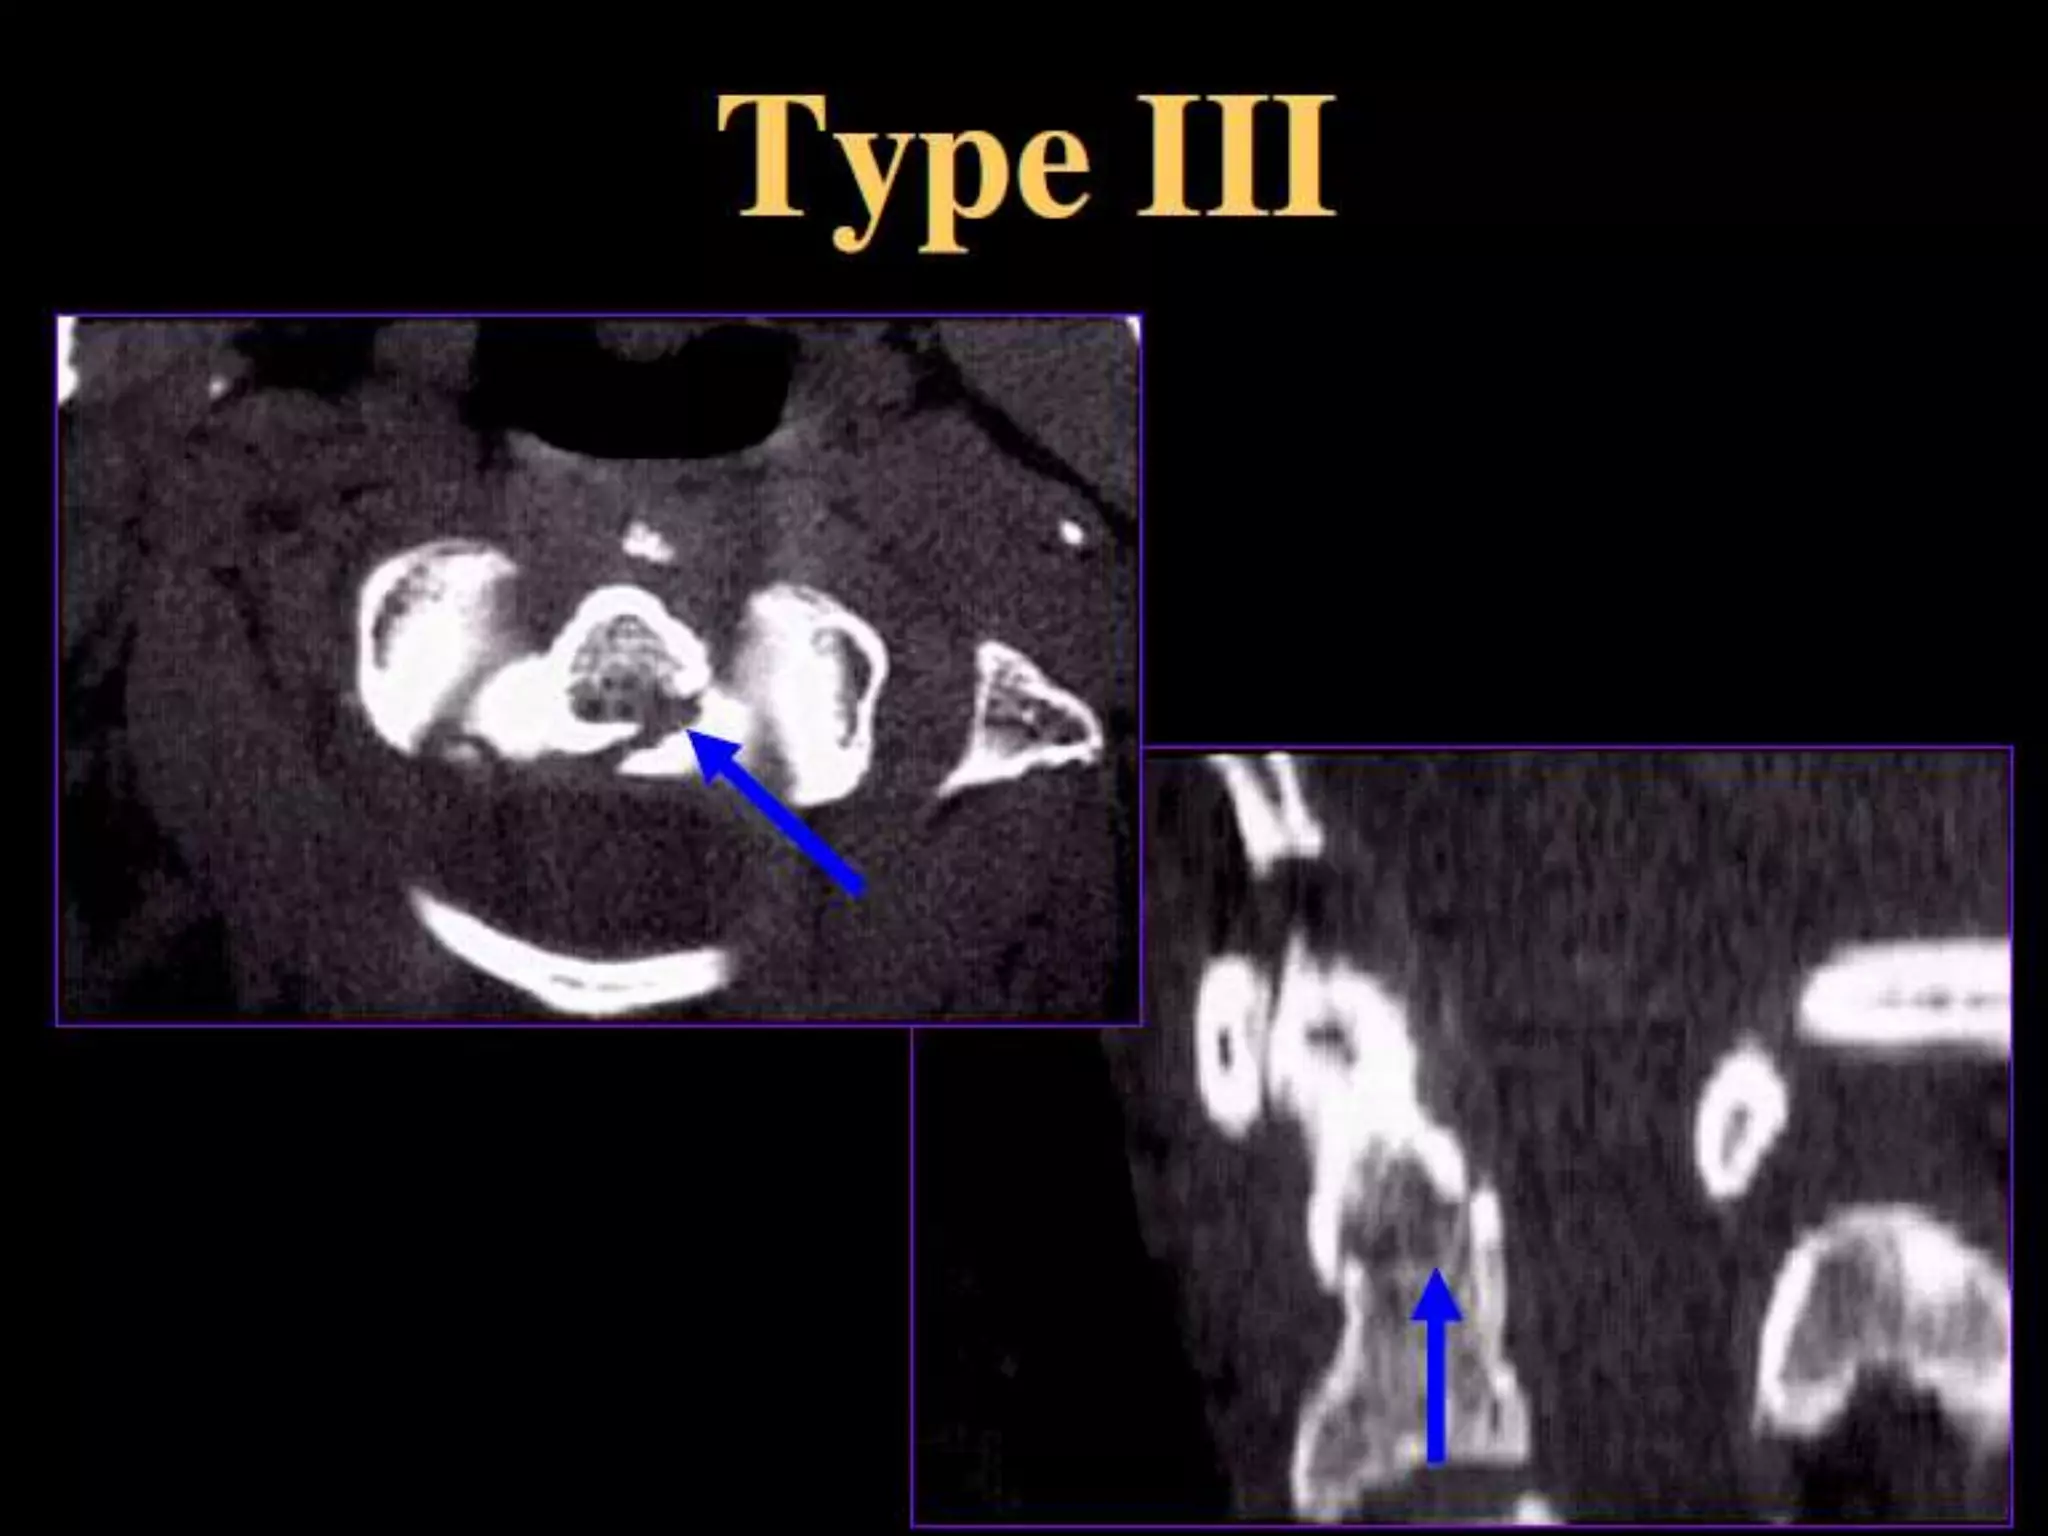

Pedicolaminar

Fracture - Separation

Type I - Articular mass FX fragment.

Type II - FX + anterior subluxation.

Type III - Type II + disc narrowing.

Type IV - Bilateral involvement with

interfacetal dislocation.

contralaterally.